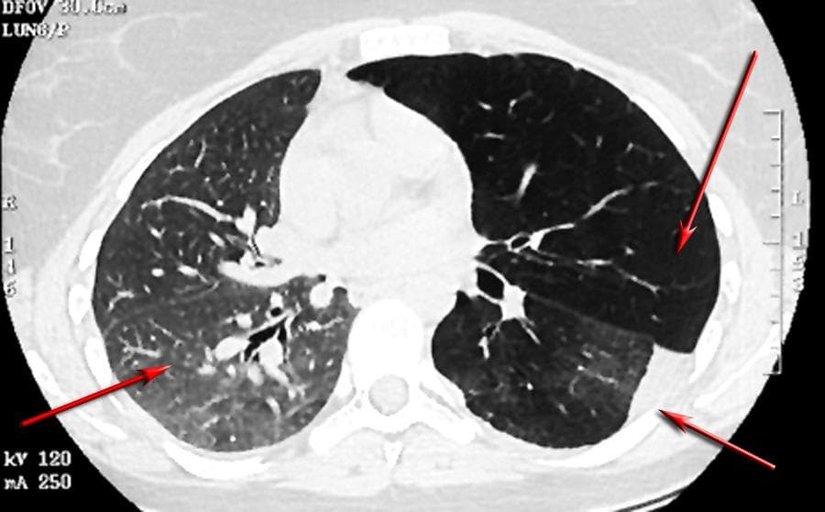

Trakeal ve Bronş Lezyonları

Çeşitli hava yolu tümörlerinin astıma benzer semptomlarla kendini gösterdiği rapor edilmiştir. Bu tümörler, aşağıdaki resimlerde gösterildiği gibi endobronşiyal karsinoid ve mukoepidermoid tümörleri içerir. Bir vakada, sol akciğerinde hiperlüsensi olan 14 yaşındaki bir erkek çocuğunun nihayetinde sol ana bronşta bronşiyal karsinoid olduğu bulundu.[119]